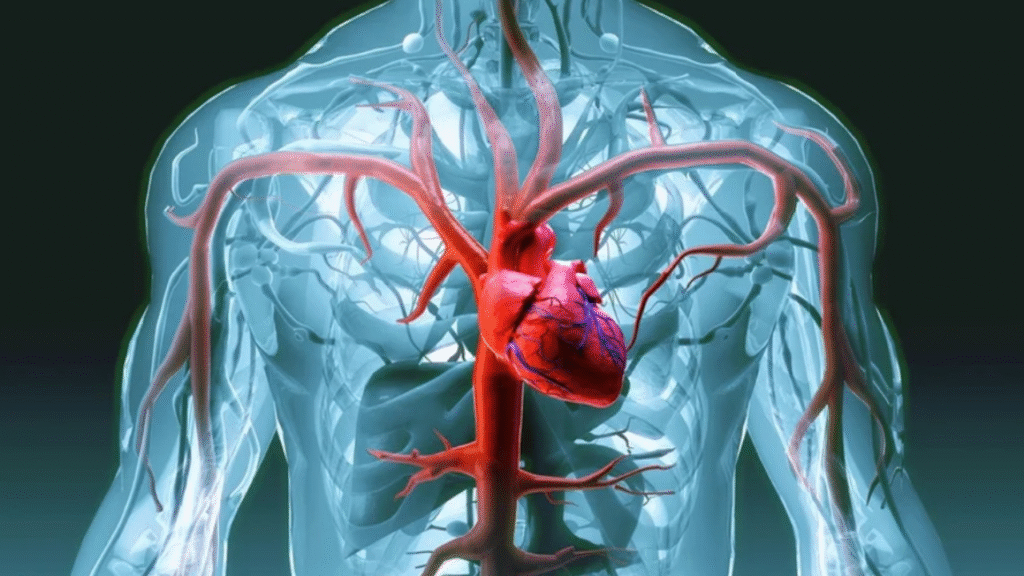

Nesta semana, a coluna Claudia Meireles abordou sobre a relação entre a cerveja e o sistema cardiovascular. Diante do interesse dos leitores, notou-se a necessidade de acionar um cardiologista para descobrir: quais são as piores bebidas alcoólicas para a saúde do coração e dos vasos sanguíneos?

Coordenador de cardiologia do Hospital Santa Lúcia Norte (HSLN), em Brasília (DF), o médico Ricardo Cals de Vasconcelos explica que o álcool gera um “efeito dose-dependente”. “Quanto maior a ingestão etílica, mais tóxico será para o coração e o sistema cardiovascular em geral”, salienta o especialista.

Segundo o cardiologista, as bebidas destiladas costumam ter 40% de álcool na composição, motivo de serem consideradas as mais perigosas para o sistema cardiovascular. “Facilmente atingem o nível tóxico para o coração”, argumenta. Essas opções incluem vodca, uísque, gin, cachaça, tequila, rum e conhaque.

O médico ressalta que essas bebidas aumentam a pressão arterial e podem desencadear taquicardia, além de elevar a glicemia e desencadear a resistência à insulina. “A parte química desses corantes industriais ocasiona problemas futuros e até câncer, nos casos de exposição exagerada”, analisa.